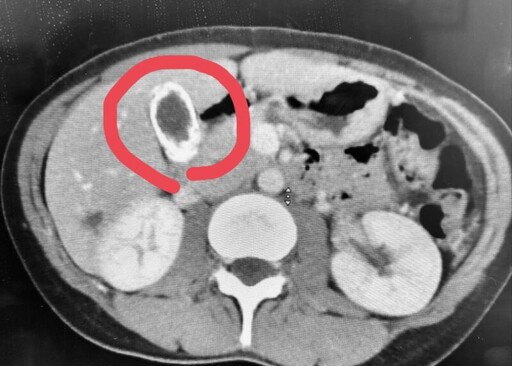

高雄市博田國際醫院肝膽胰外科近日收治一例極為罕見膽囊病變病例,病人的膽囊完全鈣化,膽囊壁宛如陶瓷般的硬殼,故醫學稱為「陶瓷膽囊」,且文獻與臨床報告顯示,陶瓷膽囊佔所有膽囊切除檢體不到1%,但合併膽囊癌機率為6%,被視為膽囊癌的高危險因子,經緊急進行膽囊切除手術,取出石頭般的膽囊。

博田國際醫院肝膽胰外科副院長李金德教授指出,30多歲的廖姓女子來自東部,自述上腹部疼痛超過一年,有時痛到背後與右肩頰骨,飯後疼痛加劇,當地醫師安排腹部超音波掃描,顯示膽囊全是結石,進一步電腦斷層檢查,驚覺膽囊壁已全部鈣化,呈現一圈白環,即為罕見的「陶瓷膽囊」影像特徵。

李金德教授緊急為廖女安排單孔腹腔鏡膽囊切除手術,提升手術安全與準確性,並搭配「靛氰綠(ICG)螢光膽道偵測定位」,讓膽管系統在手術過程中清楚可視,精準切除鈣化膽囊,手術歷時1小時,成功取出連手術刀都難以切開的鈣化膽囊。

李教授提及,從醫以來,首次收治陶瓷膽囊病例。其可能的形成病因包括:膽囊頸部結石阻塞膽囊管,導致慢性炎症;膽囊壁慢性炎症反覆發作;膽囊動脈阻塞造成局部出血,以及鈣代謝異常或膽囊內出血等因素,發病機制尚未明確,但多數病例伴隨慢性膽囊炎和膽結石,鈣化主要是碳酸鈣沉積在膽囊壁中。

早期文獻指出,被視為膽囊癌的高度危險因素,癌變率約為12.5-62%,完全鈣化因黏膜細胞已被鈣化組織取代,癌變風險較低;不完全鈣化型仍有黏膜細胞,癌變風險較高,但目前合併膽囊癌機率已降為6%。